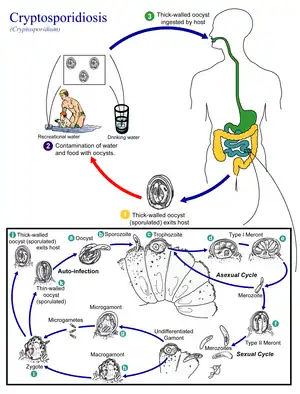

Cryptosporidium spp. exist as multiple cell types which correspond to different stages in an infection (e.g., a sexual and asexual stage).[1] As an oocyst – a type of hardy, thick-walled spore – it can survive in the environment for months and is resistant to many common disinfectants, particularly chlorine-based disinfectants.[20][21] After being ingested, the sporozoites within oocysts excyst (i.e., are released) in the small intestine. The released sporozoites subsequently attach to the microvilli of the epithelial cells of the small intestine. From there they become trophozoites that reproduce asexually by multiple fission, a process known as schizogony. The trophozoites develop into Type 1 meronts [1] that contain 8 daughter cells.[22]

These daughter cells are Type 1 merozoites, which get released by the meronts. Some of these merozoites can cause autoinfection by attaching to epithelial cells. Others of these merozoites become Type II meronts,[23] which contain 4 Type II merozoites.[22] These merozoites get released and they attach to the epithelial cells. From there they become either macrogamonts or microgamonts.[23] These are the female and male sexual forms, respectively.[22] This stage, when sexual forms arise, is called gametogony.[24]

Zygotes are formed by microgametes from the microgamont penetrating the macrogamonts. The zygotes develop into oocysts of two types.[23] 20% of oocysts have thin walls and so can reinfect the host by rupturing and releasing sporozoites that start the process over again.[22] The thick-walled oocysts are excreted into the environment.[23] The oocysts are mature and infective upon being excreted.[22]